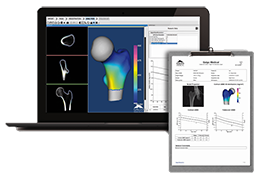

High-quality and fast 3D reconstruction and 3D rendering

Performs 3D reconstruction and volume rendering.

Side-by-side comparative assessment for pre- and post-operative scans.